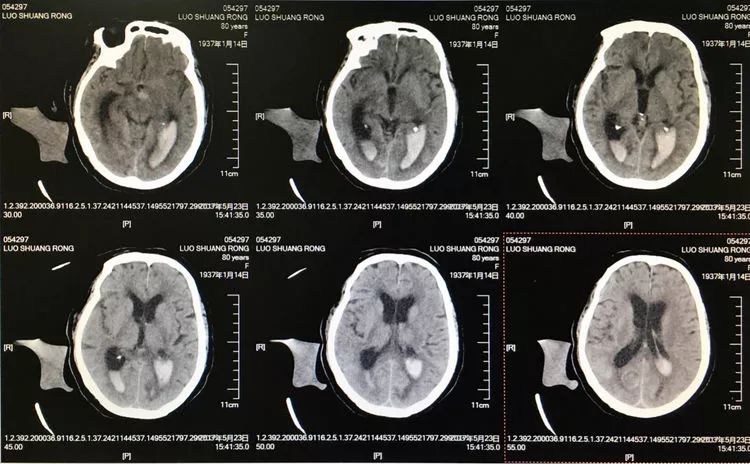

患者女性,80岁,以SAH于2017.5.20急诊入院,CTA示基底动脉顶端动脉瘤。

旋转增强器透视观察各个投照角度弹簧圈的分布情况,侧位透视发现瘤腔后部的弹簧圈分布疏松,形成死腔,看来革命还未成功,同志尚需努力呀!

回头再观察左椎动脉造影的三维成像,发现瘤腔确实有向后方突出的分叶,明确弹簧圈团后部的空虚处仍是瘤腔的一部分

此刻微导管的管头被支架压在瘤腔前部,显然无法再深入到瘤腔后部的死腔,这根直头的微导管该结束使命了,